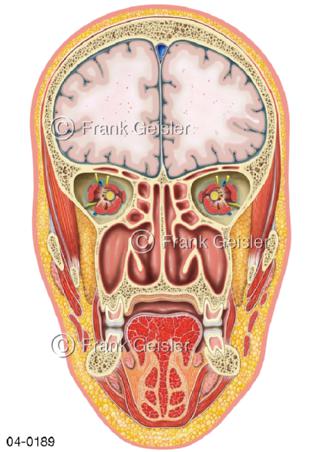

Bildergalerie Topografie Organe

Bilder zur topografischen Anatomie, die Lage der Organe und die Strukturen nach ihren räumlichen Lagebeziehungen zueinander, Übersicht der inneren Organe im Kopf und im Rumpf, Topografie der Organe im Brustraum (Thorax) und im Bauchraum (Abdomen)